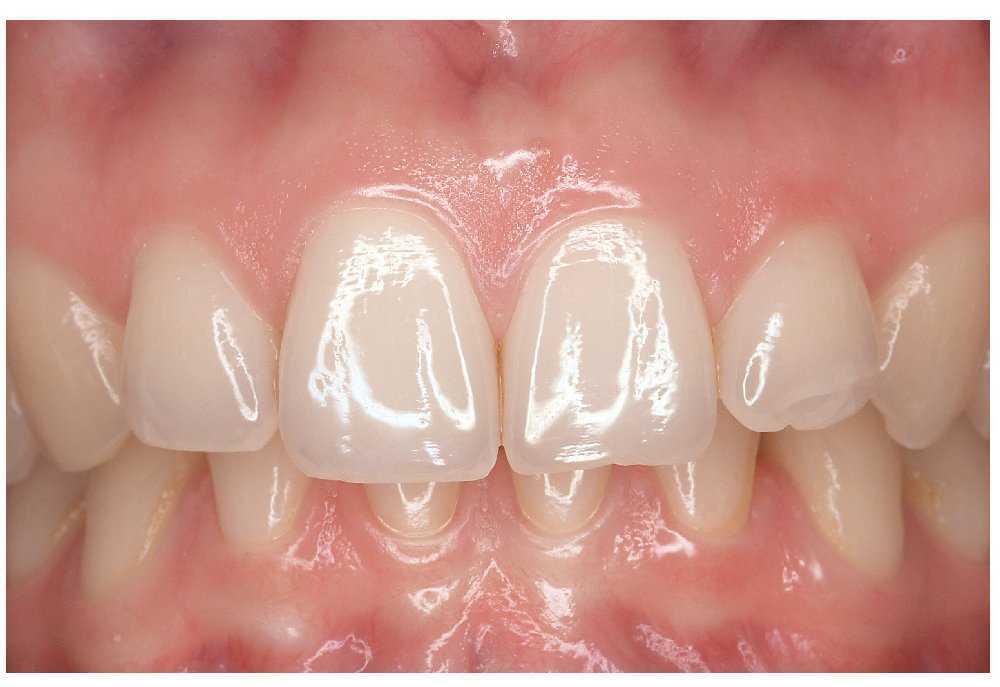

El tono rosado de la mucosa normal se debe a que el epitelio deja traslucir el tejido muy vascularizado subyacente. En general, se acepta que cuanto más grueso es el epitelio y menor es la perfusión subepitelial más pálida es la mucosa. Incluso la mucosa normal muestra tonalidades diversas. La encía insertada es más clara que la encía libre (fig. 13) y el paladar duro más queratinizado también es de un color más claro que el paladar blando.

Figura 13. La encía insertada, más queratinizada, es de una tonalidad más clara que la encía libre.